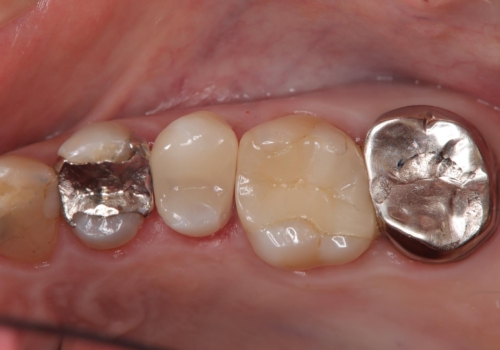

- 金属の詰め物が外れた状態で長期間過ごされた患者様が、歯を治したいとのことで来院されました。良好な長期予後が期待でき、歯質をできるだけ残せるセラミック治療を即日で行いました。

治療途中で虫歯も綺麗に除去しています。術後経過良好で、患者様も満足されています。他にも治療が必要な虫歯がありますので、順を追って治療する予定です。